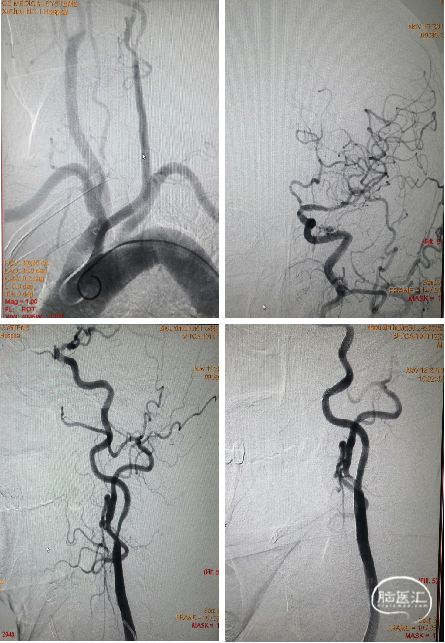

替罗非班经静脉7ml/h维持,10min后经导引导管于颈总动脉造影显示:颈内动脉起始部重度狭窄,远段血通畅,(mTICI评分3级)。为降低风险,决定二期处理颈内动脉狭窄。

术后2月来院复查造影:左侧颈内动脉起始部狭窄严重,左侧大脑中动脉M1段血流通畅。予以植入颈动脉支架。